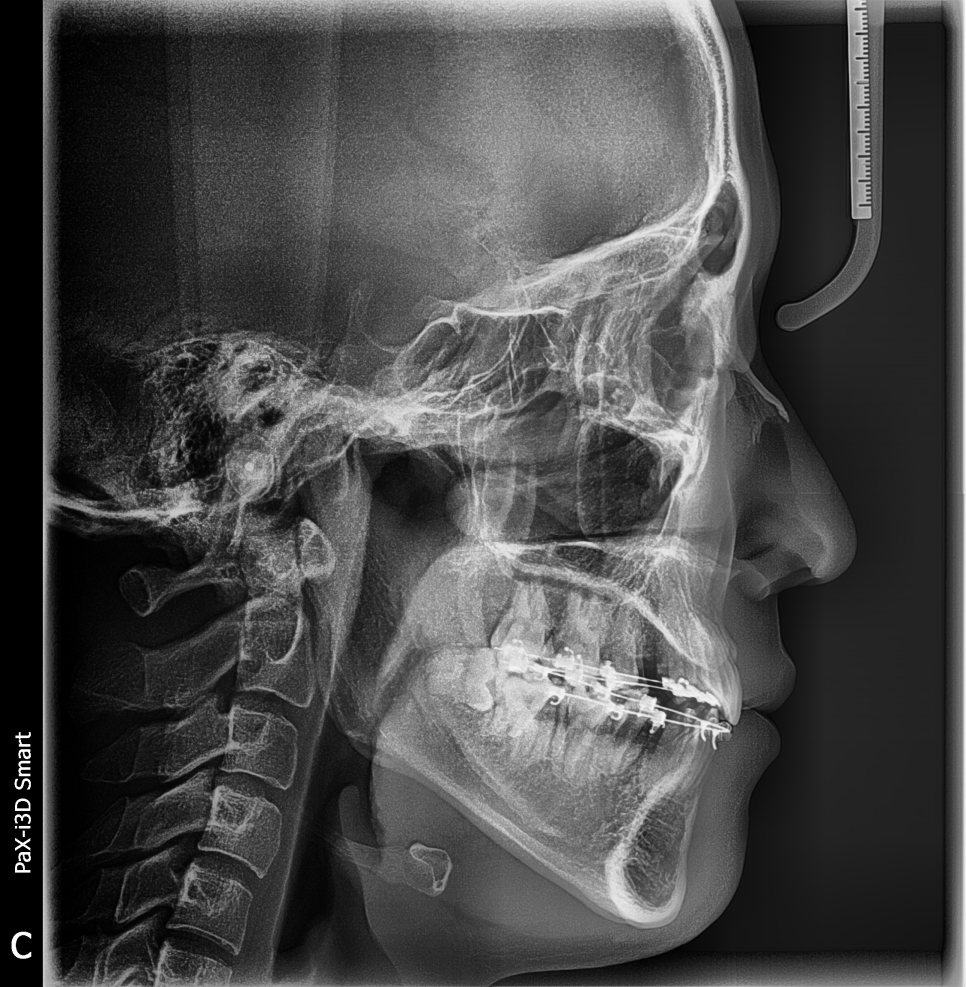

투디치과 최대리님 교정 중간점검 사진

나중에 교정마무리 되시면 전후 사진으로 좀 더 정확하게 비교해서 보여드릴게요^^